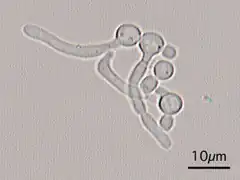

Um tubo germinativo é um prolongamento produzido por esporos de fungos durante a germinação.

O tubo germinativo diferencia-se, cresce e desenvolve-se por mitose para criar hifas somáticas [en].[1]